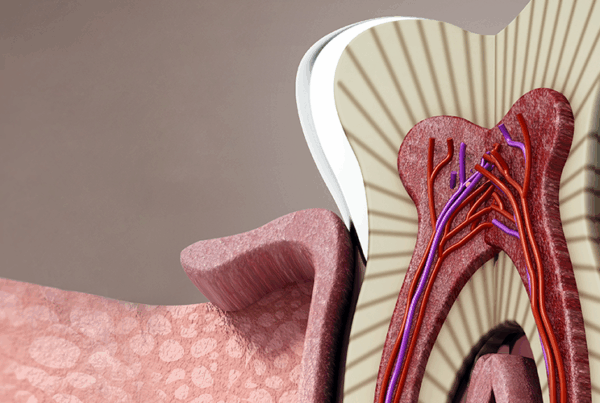

Impacted wisdom teeth occur when the last set of molars, commonly known as wisdom teeth, fail to fully emerge or align properly with the rest of your teeth. These teeth typically appear in late adolescence or early adulthood, around the ages of 17 to 25. However, due to various factors, they may not have enough room to grow in naturally. This lack of space often causes them to become trapped—or “impacted”—beneath the gum line or against other teeth.

The reasons for impaction can vary. One of the most common causes is insufficient jaw space; as human jaws have evolved to become smaller, there’s often not enough room to accommodate these third molars. Additionally, wisdom teeth might grow at awkward angles, tilting forward, backward, or even sideways, which can further prevent them from emerging correctly. In some cases, genetic factors or the presence of cysts or tumors can also contribute to impaction.

When wisdom teeth remain partially or fully trapped under the gum, they can lead to a variety of issues. Mild discomfort is often the first sign, but if left untreated, impacted wisdom teeth can cause serious complications. These may include infections, as bacteria can easily become trapped around the partially erupted tooth, leading to gum disease or even abscesses. Impacted teeth can also exert pressure on adjacent teeth, causing crowding, shifting, or damage to other healthy teeth. In severe cases, this pressure can result in the development of cysts or tumors, which can damage the jawbone and surrounding tissues.